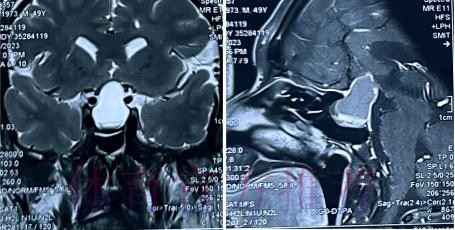

从恐慌到冷静 影像学检查给出的真实答案

在高速对抗的现代足球里 现场肉眼和赛后情绪往往会放大对伤情的判断 一名球员倒地呻吟或无法坚持比赛 很容易被解读为韧带断裂 或肌肉严重撕裂 但真正决定恢复周期的关键因素 通常要到核磁共振检查之后才会明朗 因为核磁能在较早阶段清晰显示软组织 肌肉 韧带以及骨结构的微小损伤情况 对伤情做出更接近真相的分级判断 塞巴略斯此次就是典型案例 初步观感可能让人联想到更严重的伤病 但核磁提示伤情相对可控 没有出现完全断裂或大面积撕裂 也就意味着他不需要漫长的康复旅程 只要遵循医学建议 科学负荷管理 就有机会用较短的时间重新回到训练场和比赛中

塞巴略斯这一类型的技术中场 通常触球频繁 变向急促 需要大范围穿插跑动 在这种比赛习惯下 肌肉和韧带承受的累积负荷极高 尤其在密集赛程和高压对抗中 任何一次小小的失衡或强硬对抗 都可能放大为潜在伤病 因此外界对他伤情格外敏感 并非夸张反应 而是基于过往大量案例得出的经验判断 从厄德高 德布劳内 再到其他同类型中场 很多球员都在职业生涯某个阶段与伤病长期共存 一旦错过最佳治疗和恢复窗口 轻伤有可能拖成旧患 进而影响球员的爆发力 节奏控制能力乃至职业寿命 在这一背景下 经核磁共振检查确认 塞巴略斯伤情没有预期严重 其实反映的是球队在医疗体系 与负荷管理上的相对成熟 至少在第一时间 做到了科学评估 而不是情绪化处理

足球历史上 不乏因为伤情评估偏差而延误治疗的例子 某些球员在初诊时被认定为普通拉伤 结果因为没有进行完整的核磁共振检查 继续带伤出战 最终发展成严重撕裂 被迫长时间缺阵 从竞技层面来看 一次错误判断 可能直接改写一个赛季的走向 也可能在球员的职业生涯里留下不可逆转的隐患 与这些案例对照 塞巴略斯这次的过程显得更为规范 受伤后迅速接受医学影像检查 医疗团队根据结果评估伤情等级 给出清晰恢复计划 俱乐部层面则通过官方渠道适度释出消息 在 保护隐私与满足公众关切之间 取得平衡 对比之下 可以看出 现代职业俱乐部在伤病管理上的专业程度 已远超十几年前更多依赖经验和肉眼判断的时代 同时也提醒公众 不要被比赛画面中的瞬间表现完全左右 而是学会等待更权威的医学信息

经核磁共振检查确认 塞巴略斯伤情没有预期严重 这一结果从某种意义上是一种系统胜利 首先是医疗系统的胜利 医疗团队在第一时间介入 选择最合适的影像学手段 明确伤情边界 避免了盲目乐观或过度保守 其次是管理系统的胜利 俱乐部没有急于利用球员的意愿 扮演所谓硬汉形象 而是尊重科学节奏 为他预留足够的恢复空间 再次是沟通系统的胜利 球员 经纪人 医疗小组和教练组之间保持信息畅通 能够在保护球员未来和保证球队眼前成绩之间找到平衡点 正是这些系统共同作用 才让一次看似危机四伏的受伤 逐步转化为可控 可恢复的阶段性波折